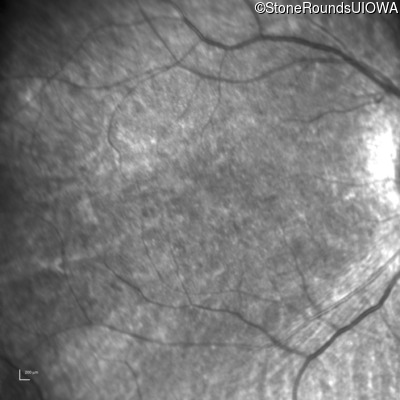

Age at visit: 10 years

Age at visit: 11 years

Age at visit: 12 years

Age at visit: 13 years

Age at visit: 14 years

Age at visit: 16 years